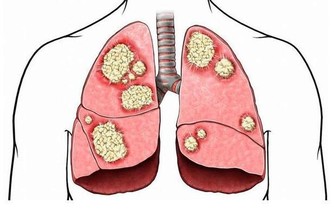

目前,在全世界範圍內仍缺乏根治HIV感染的有效藥物,也無預防艾滋病的有效疫苗,因此最重要的是採取預防措施,其方法是:

1、正確使用安全套:

性傳播是艾滋病傳播中最常見的,所以正確使用安全套是性生活中最有效的預防措施之一。

2、嚴禁吸毒:

吸毒不僅違反法律,還會危害生命,感染艾滋病毒的機率也會大大增加,因為吸毒者免疫機制很差,非常有利於艾滋病病毒的侵襲。

3、不共用注射器:

共用注射器是很危險的,如果注射器中帶有艾滋病病毒,病毒很容易隨著輸液進入人體。

4、切斷血液傳播:

不要擅自輸血和使用血製品,要在醫生的指導下進行,以免感染。